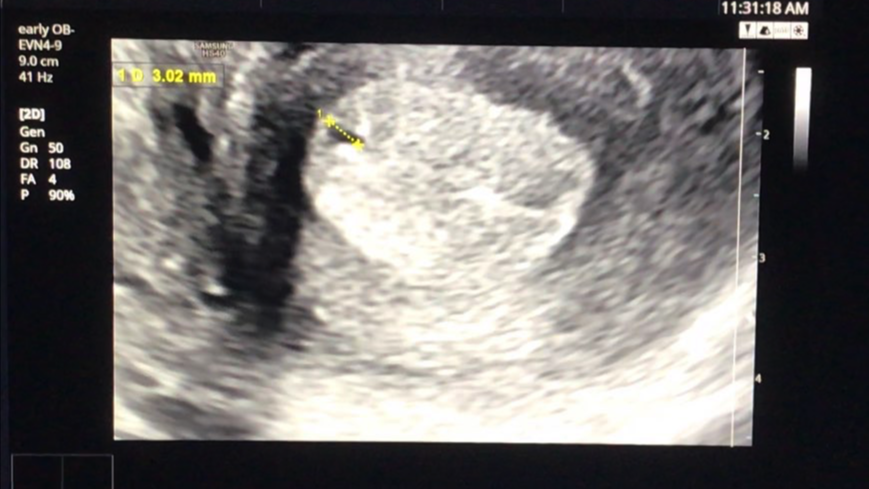

그리고 선생님은 초음파를 보면서 어떤 상태인지 한번 자세히 보자고 말씀하셨습니다.

아직은 확실하게 '아기집이 이거다!' 하고 보이지는 않는 상태이지만 와이프의 몸 안에 무언가가 생기기는 했나 봅니다.

확실히 아기집이 생겼다고 말씀을 안 해주시는 걸 보면 원장님 또한 아직은 조심스러운 상태이신 게 맞는 것 같습니다.